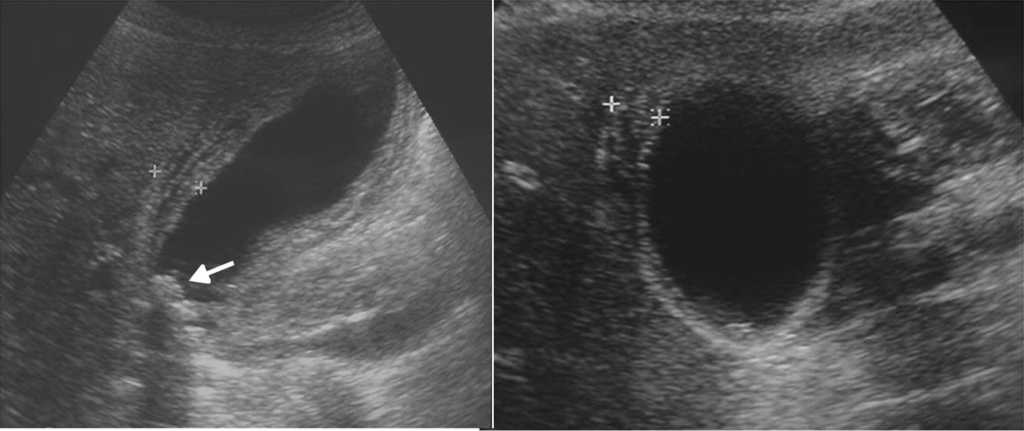

C??lico renal

Cuando hay sospecha de enfermedad liti??sica renal, las im??genes deben acompa??ar y seguir a una exhaustiva exploraci??n cl??nica16. El ultrasonido, para ello, es el primer m??todo de elecci??n porque confirma el diagn??stico de litiasis, estableciendo su tama??o y localizaci??n, excluye otras causas de dolor abdominal y confirma o descarta la hidronefrosis17. Adem??s, identifica c??lculos en los diferentes grupos caliciales, en la pelvis y en la uni??n pieloureteral o ureterovesical16 (fig. 12).

Los c??lculos se visualizan f??cilmente con el ultrasonido cuando generan sombra ac??stica posterior, pero a veces por su tama??o peque??o o el tejido circundante se dificulta su reconocimiento. En estos casos, el artefacto de centelleo en el Doppler color, consistente en la alternancia de color por detr??s de la litiasis, permite hacer el diagn??stico y aumentar la sensibilidad ecogr??fica en b??squeda de litiasis18 (fig. 13)